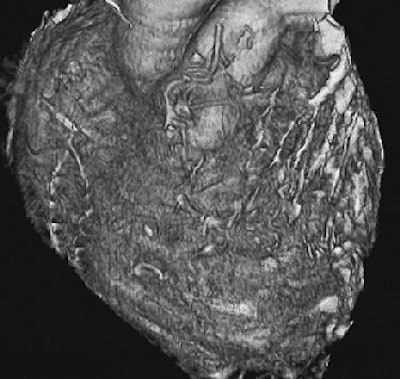

| Minimization of stepladder artifacts with maintenance of an optimal heart rate and selection of an optimal reconstruction window. Volume-rendered images reconstructed from data acquired at 40% (a, above) and 70% (b, below) of the R-R interval, with a heart rate of 55 beats per minute, show a stepladder artifact, which is less pronounced in (b). Note also the improved depiction in (b) of patency both in the in situ graft of the left internal mammary artery to the distal left anterior descending artery (arrowhead) and in the Y-graft (straight arrow) of a radial artery from the left internal mammary artery to the diagonal artery (curved arrow). Figure 5a, b, Choi HS, Choi BW, Choe KP, et al. Pitfalls, artifacts, and remedies in multi-detector row CT coronary angiography. RadioGraphics 2004; 23:787-800. |